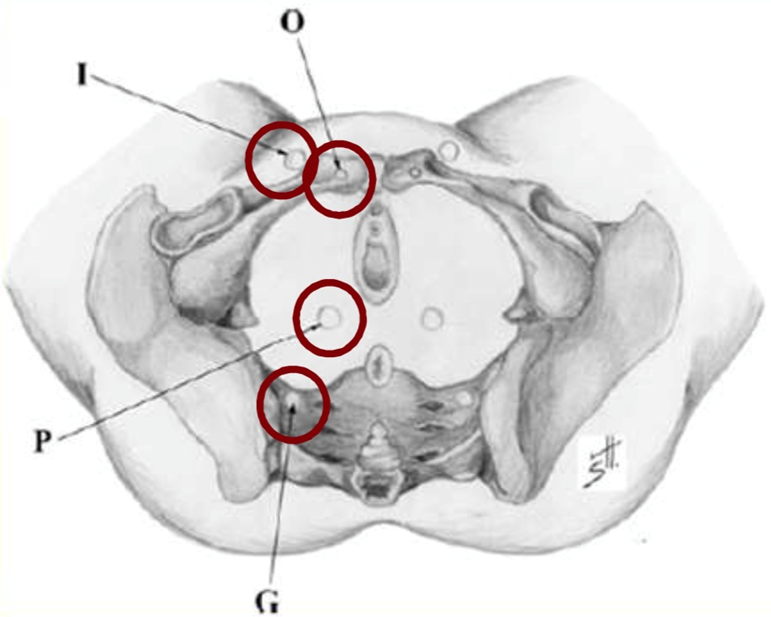

盆腔高压血液通过特定通道“逃逸”至体表,形成非典型静脉曲张:

I 点(Inguinal point):腹股沟管 → 腹壁/大腿根部曲张;

O 点(Obturator point):闭孔静脉 → 大腿内侧疼痛/曲张;

P 点(Perineal point):会阴静脉 → 会阴部曲张;

G 点(Gluteal point):臀下静脉 → 臀肌疼痛、坐骨区曲张。